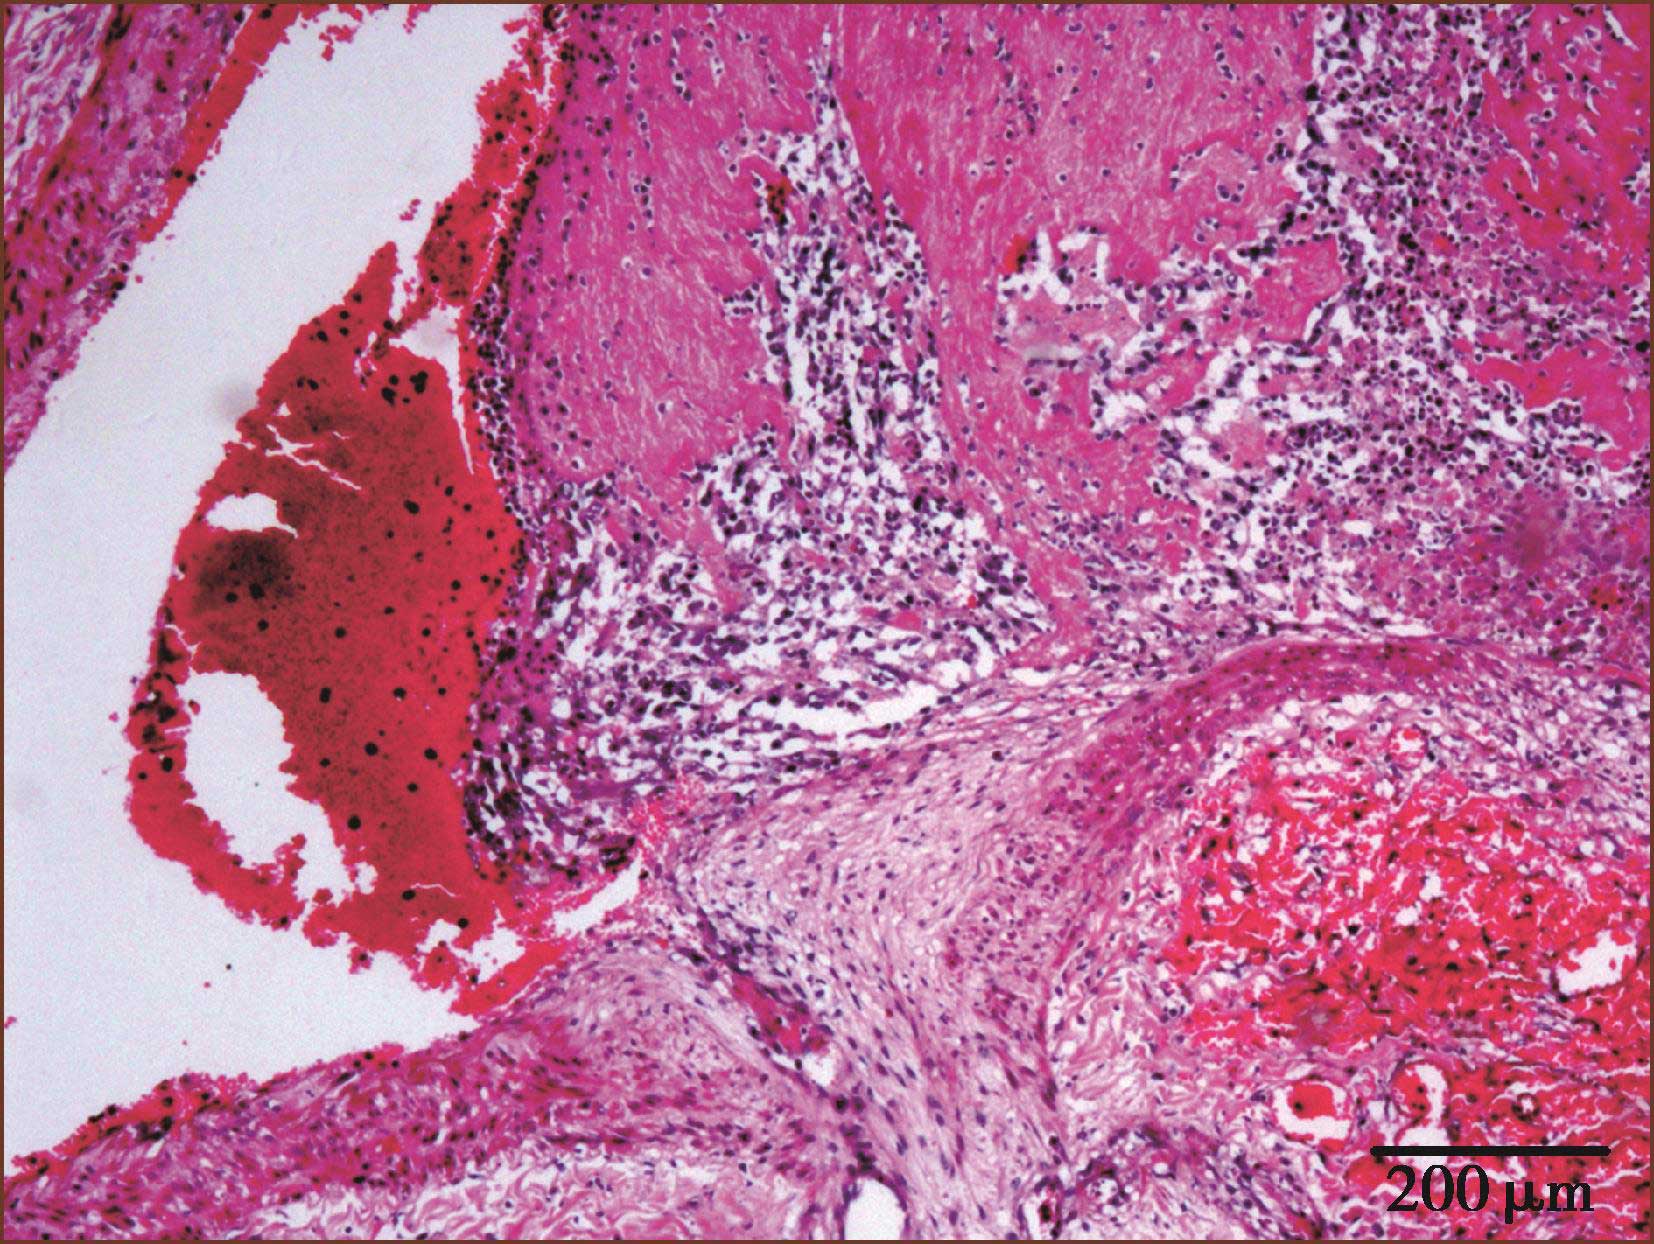

(一)肺动脉栓塞的类型及病理形态

引起肺动脉栓塞主要的原因是下肢深静脉血栓脱落,不同口径的肺动脉栓塞产生的结果也不同。外周肺小动脉栓塞常常没有症状,只在尸检时偶然发现。反复发生的肺小动脉栓塞会引起肺动脉高压。大的肺动脉血栓栓塞会引起右心功能衰竭、低血压和循环衰竭而猝死。病理学上,急性肺动脉血栓栓塞,肉眼及显微镜下可见左、右肺动脉及肺内小动脉内充满暗红色血栓物质(图3-2-1, 图 3-2-2)。

图3-2-2 较大肺动脉内充满新鲜血栓(主要含纤维素、白细胞)(HE染色,低倍放大)

慢性栓塞时,肺动脉内膜增厚,多为机化血栓(图3-2-3)。血栓可以再通,在原有机化血栓基础上又可见新鲜血栓形成(图3-2-4,图3-1-8)。

图3-2-3 肺动脉血栓机化(HE染色,低倍放大)

图3-2-4 肺动脉内新鲜及机化血栓(HE,低倍放大)